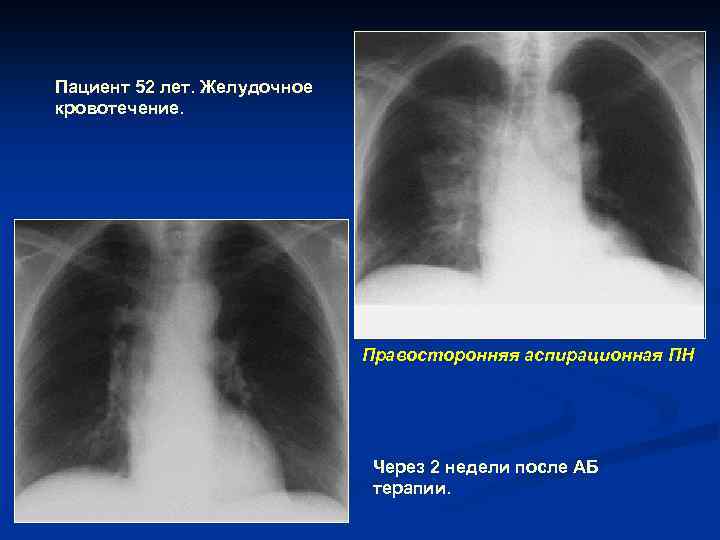

Пациент 52 лет. Желудочное кровотечение. Правосторонняя аспирационная ПН Через 2 недели после АБ терапии.